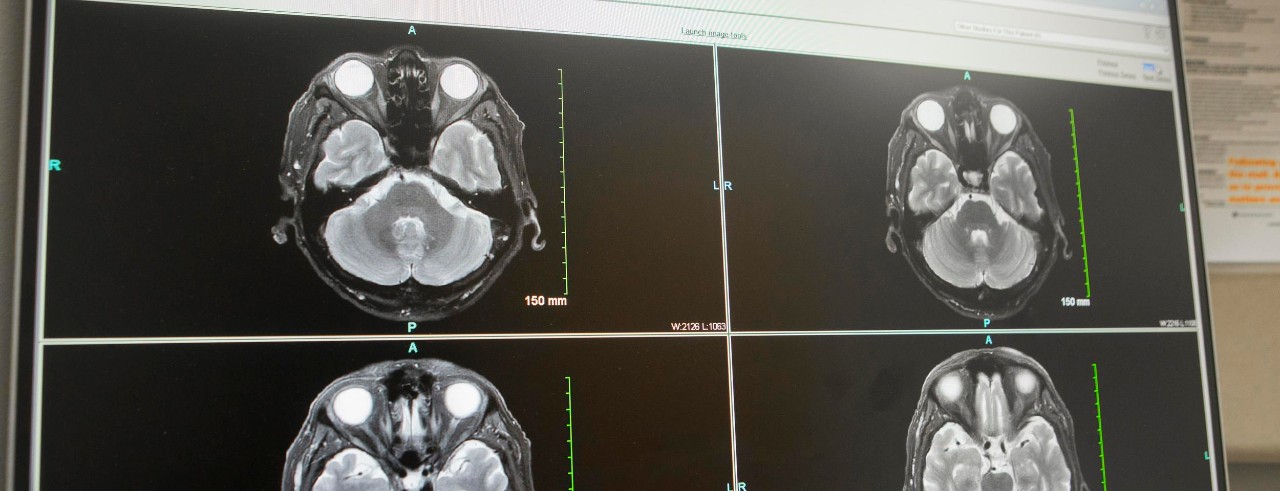

Endovascular thrombectomy is a minimally invasive procedure for acute ischemic stroke patients that uses a catheter to remove a blood clot from a blood vessel in the brain, which restores blood flow. Patients with strokes with a large ischemic core were previously not considered candidates for thrombectomies because of concerns of an increased risk of hemorrhage, disability and death.

"These are patients who have very large areas of clear hypodensity on the baseline image (brain already dying or dead)," Broderick said. "These patients do not benefit from reperfusion with lytic drugs or endovascular therapy."

Featured photo at top of brain scans. Photo/Joseph Fuqua II/UC Marketing + Brand.